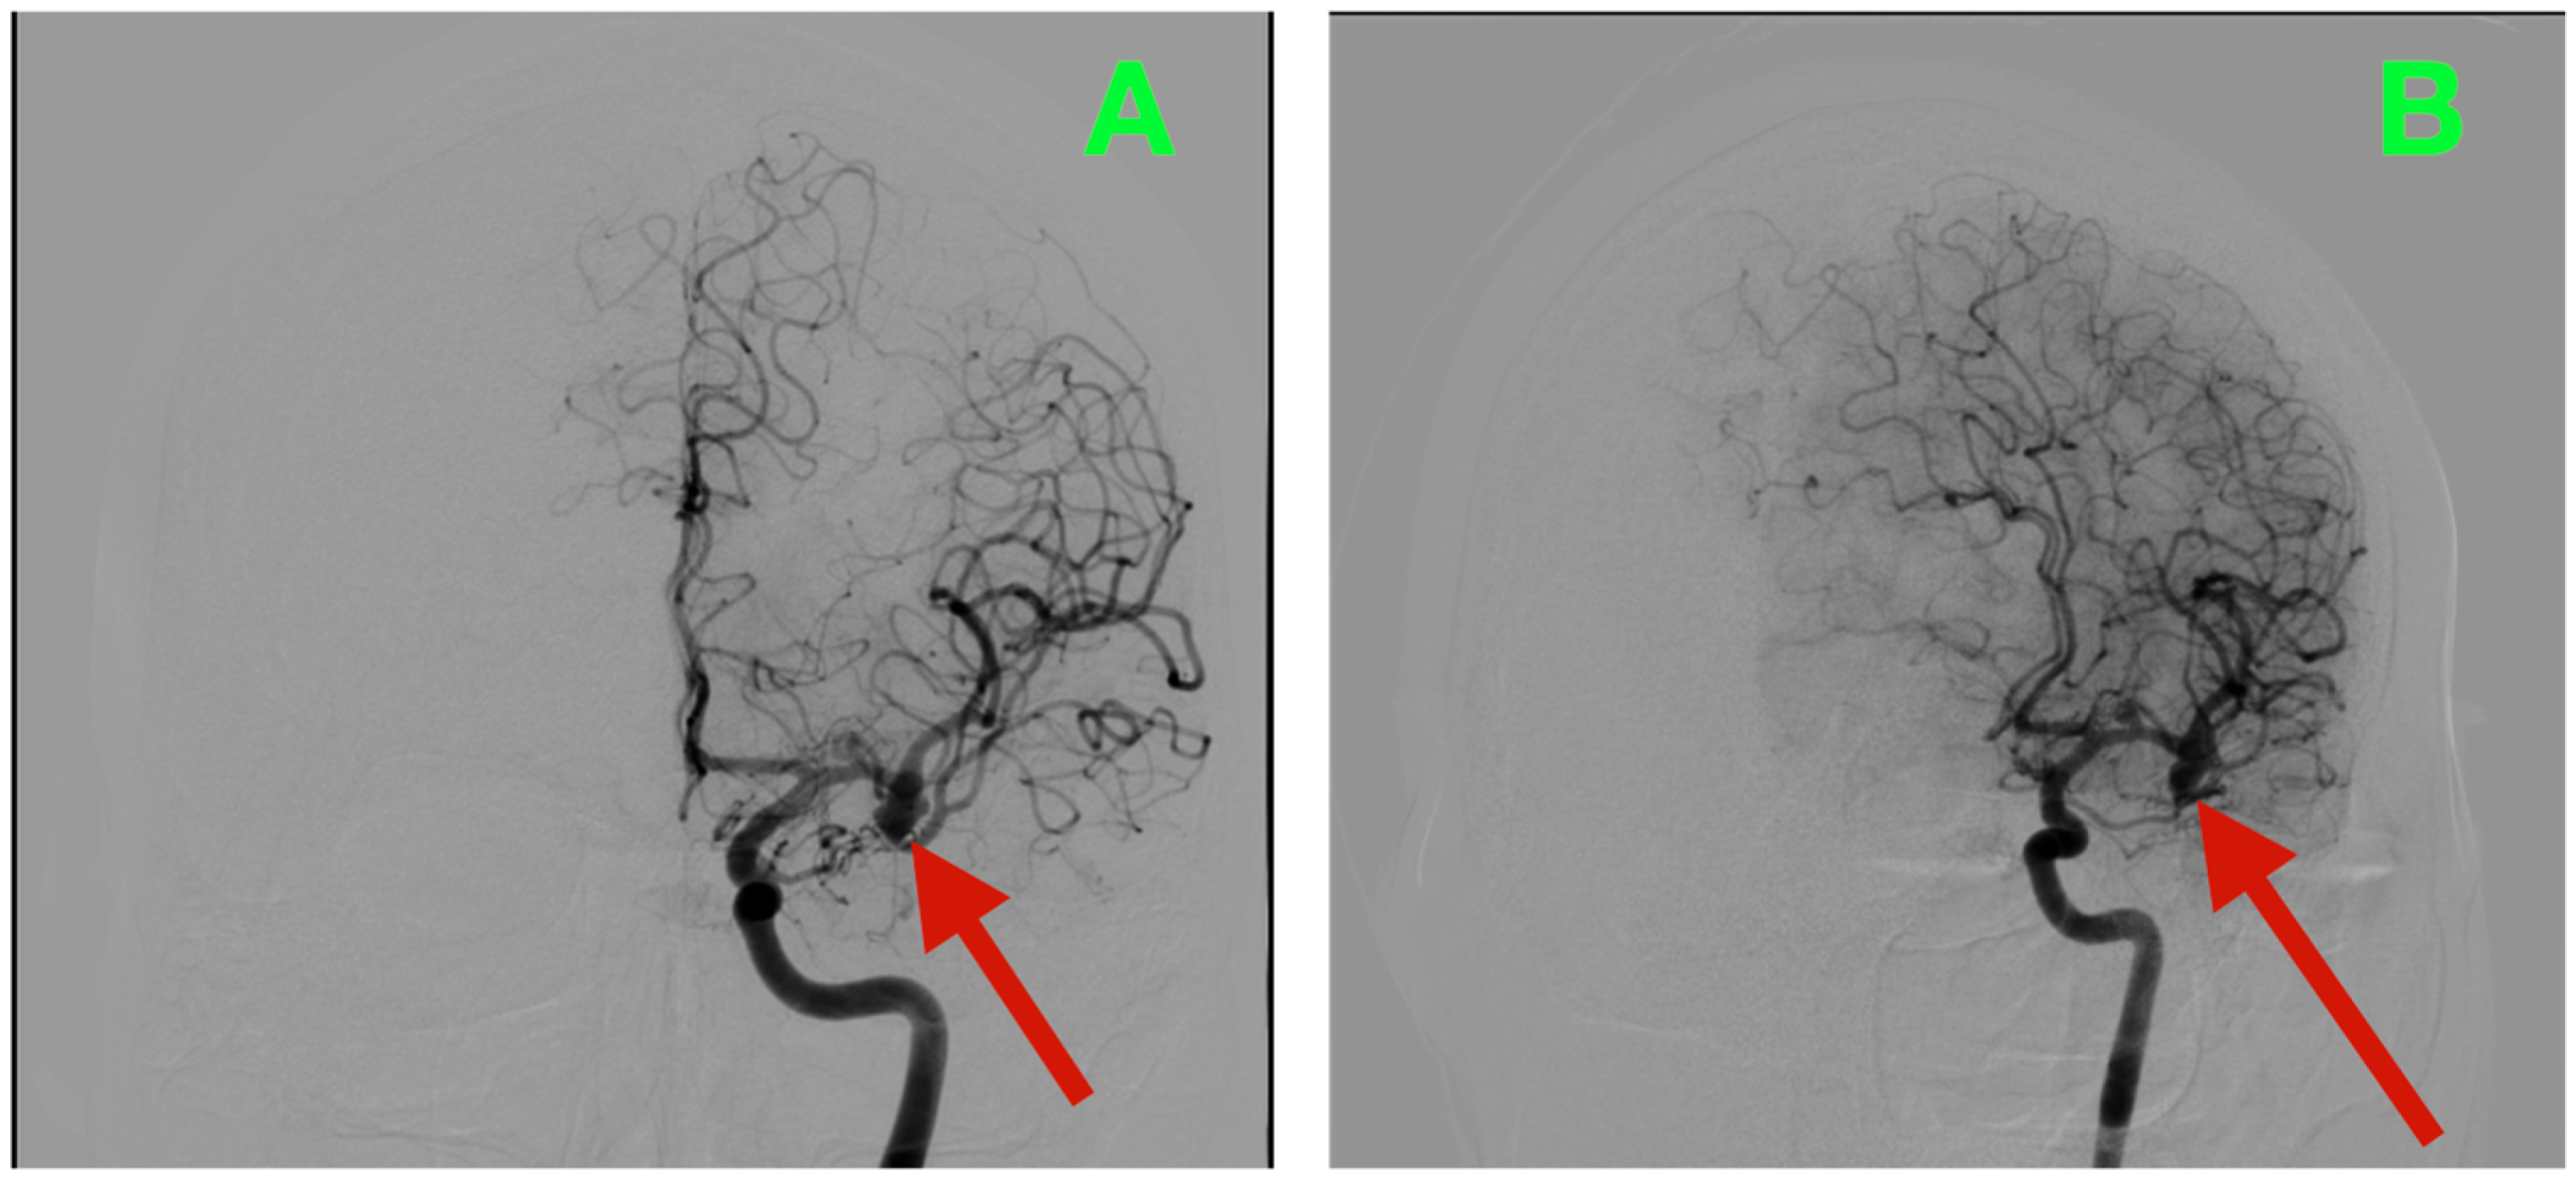

Biplanar DSA of the left internal carotid artery (ICA) was performed under stringent hemodynamic factors to avoid iatrogenic rupture, revealing a tandem aneurysmal arrangement at the proximal MCA (Figure 1A,B). The parameters allowed a frame-by-frame hemodynamic acquisition that indicated peak opacification of the M1 segment at 2.35 s, with complete venous phase clearance at 5.92 s. Both transit times are well within normal values, thus preserving proximal inflow but inducing concern for turbulent microhemodynamics to the aneurysmal neck. The dominant lesion arose exactly at the M1 bifurcation when the parent segment bifurcated into the superior and inferior M2 segments. The aneurysmal neck demonstrated a broad neck diameter of 4.20 mm at its maximal width and bridged the saddle point of the bifurcation, with both M2 origins being partially within the base of the aneurysm. The dome had a maximum height of 4.37 mm, which extended anterosuperiorly and had a slight lateral component toward the opercular−insular boundary. In the sagittal plane, the axis of the dome was at a 43° angle to the M1 axis and 18° in a lateral direction, placing the sac in millimetric proximity to the insular apex and under the lip of the opercular cortex, with only 2.6 mm of distance to the shortest opercular vein—a member of the superficial Sylvian venous complex—the preservation of which was critical to maintain the cortical venous drainage during the surgical dissection of the venous complex. There was subtle lobulation of the contour of the anterosuperior dome, which is a morphological characteristic that occurs with focal wall remodeling under the conditions of chronic high-impulse hemodynamic loading. Proximal to the bifurcation aneurysm and at 3.9 mm from the carotid terminus, a second and much smaller lesion was demonstrated on the dorsal wall of the M1 segment. In stark morphological contrast, this aneurysm was fusiform, which expanded the vessel circumferentially without a neck. The maximum dimensions were 3.12 mm in length, 2.39 mm in width, and 2.45 mm circumferentially. The location was particularly troublesome, as it was buried within the lenticulostriate perforator belt. At least three perforators were clearly demonstrated as arising from the aneurysmal wall and had diameters between 320 and 480 μm, with each perforator draping posteriorly toward the anterior perforated substance. Preoperative assessments, along with the measured flow profiles of the internal carotid artery, indicated that the vessels supplied the superior posterior limb of the internal capsule, the head of the caudate nucleus, and the lateral anterior putamen—all locations where damage could yield limited control of the contralateral hemiplegia and devastating losses in higher-order motor integration.

Figure 1.

Preoperative DSA of the left internal carotid artery. (A) Anteroposterior view demonstrating a broad-necked saccular aneurysm arising from the M1 bifurcation, incorporating the origins of both superior and inferior M2 trunks, with an anterosuperior dome projection toward the opercular–insular interface. Proximal to the bifurcation, a fusiform dilation of the dorsal M1 segment is visible within the lenticulostriate perforator belt. (B) Lateral projection further delineating the dome axis in relation to the insular apex and overlying opercular cortex, as well as the proximity of the fusiform lesion to perforators supplying the posterior limb of the internal capsule and dorsal basal ganglia.